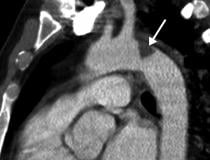

This photo gallery shows the variety of radiological presentations of COVID-19 (SARS-CoV-2) in medical imaging, including computed tomography (CT), radiograph X-rays, ultrasound, echocardiograms and magnetic resonance imaging (MRI). The radiology images show examples of typical COVID pneumonia in the lungs and the numerous complications the virus causes in the body in multiple organs, including the brain, kidneys, heart, abdomen and vascular system.